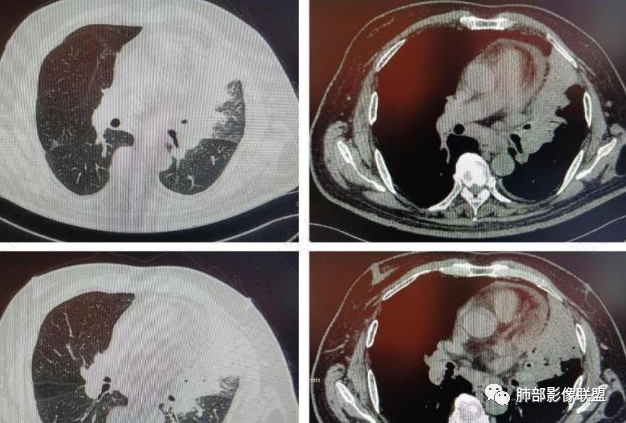

三、影像表现:左肺上叶多发片状高密度影,散在,边缘模糊,支气管壁稍增厚,中轴间质、小叶间隔增厚、有结节感,左肺上叶前段病灶可见胸膜增厚,部分小支气管不能分辨;右肺上叶后段混合磨玻璃结节,边界清,邻近胸膜凹陷;纵膈淋巴结肿大;心包增厚;左侧少量胸水。此外,扫及右侧胸腔内甲状腺肿;左侧肩胛骨旁肌群内脂肪瘤。

四、综合分析:老年男性,以咳嗽咳痰为主要临床表现,无发热,白细胞正常,影像表现为左肺上叶片影,前段结节影、胸膜增厚、部分小支气管不能分辨。左肺上叶中轴间质增厚、小叶间隔增厚、结节感,肺门纵隔见肿大淋巴结,尽管肺部病病灶边缘特征不典型,但高度疑及癌性淋巴管炎这一“次生灾害”却具有相当重要提示意义,而肺癌中最常伴癌淋的就包括腺癌。右肺上叶后段混合磨玻璃结节,边界清楚,张力明显,具有一定特征性,高度指向浸润性腺癌。这对于左肺病灶具有一定程度“助攻”效应。总体而言,本例左肺病灶的诊断关键点在于判断出癌性淋巴管炎。癌性淋巴管炎的结节在外围间质多见,小叶间隔可呈串珠状、结节状增厚,由于出血及水肿,小叶间隔增厚较明显,或呈不规则增厚。有的肺小叶呈多角状阵列。常合并胸水。

图1、2为同一病例,左肺下叶背段周围型肺Ca并左肺下叶局限型PLC,肿块与左下肺门间肺纹理不规则增粗,肿块与膈面有串珠样高密度影相连。图3为乳腺癌化疗后多发转移并弥漫型PLC,双肺多肺叶肺纹理不规则增粗增多并多发微小结节,其中右肺上叶后段肺纹理多呈典型的“毛刷征”,双肺上叶胸膜下区可见多发垂直于胸膜的不规则增厚的小叶间隔及微小结节。图4为右肺上叶周围型肺癌并弥漫型PLC,左肺上叶背段肺纹理不规则增粗增多呈典型的“毛刷征”,右侧叶间胸膜轻度增厚及多发微小结节。图5为胰腺癌术后多发转移并弥漫型PLC,双肺广泛肺纹理增多增粗并多发微小结节,双肺胸膜下多发肺小叶间隔增厚并见微小结节;图6(MPR冠状位)为食管癌术后肺弥漫型PLC,左肺广泛肺纹理不规则增多、增粗及多发小结节,边缘模糊。